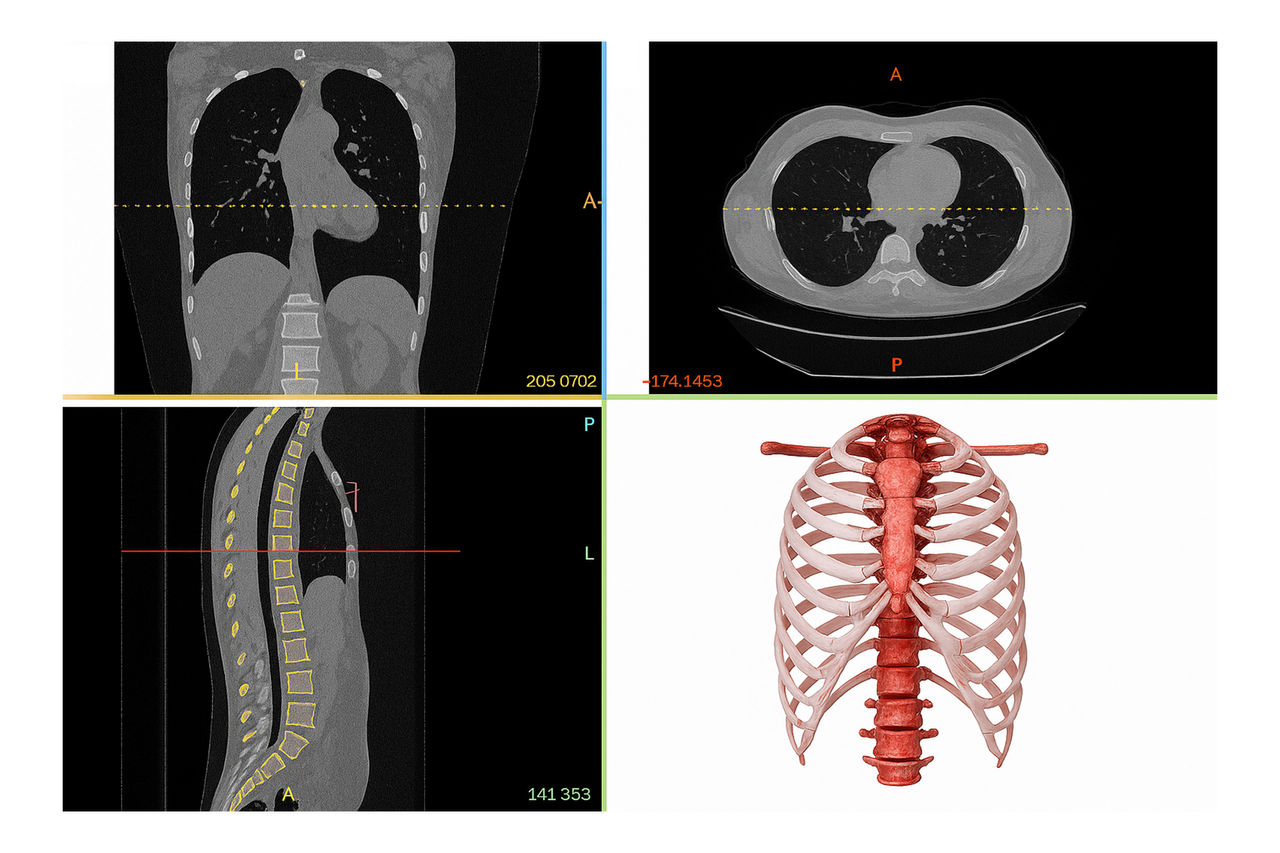

The 3D Printing & Advanced Image Post-Processing Lab at Nemours Children’s in Central Florida transforms CT and MRI scans into detailed, patient-specific 3D models. These models help clinical teams prepare for complex procedures and give families clearer, more tangible ways to understand their child’s condition.

Pediatric anatomy can vary greatly, especially when congenital differences are involved. Traditional 2D imaging may not fully capture the subtle spatial relationships that guide surgery. Holding and examining a physical model makes it easier for clinicians to visualize critical structures and plan the safest, most effective approach.

Our lab uses Food and Drug Administration (FDA)-cleared segmentation software and advanced 3D printing technology to create high-quality models that reflect each patient’s unique anatomy. We work closely with pediatric specialists across Nemours to support clinical planning, education, and research.

Our lab is built around high-performance imaging workstations designed for pediatric anatomy. We use FDA-approved software to isolate bones, vessels, soft tissues, and other structures from CT and MRI scans. This precise digital segmentation creates the foundation for everything we produce, from digital visualizations to physical models.

2. Segmentation & Refinement: We isolate relevant anatomy using FDA-cleared tools.

3. Digital Reconstruction: A detailed 3D model is created for review.